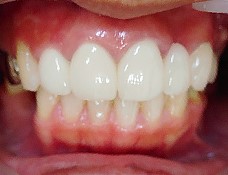

- ブリッジ 症例写真 B-0111フルジルコニア7本 女性モニターの方です。

この方は奥歯に虫歯と歯の欠損がありました。 上下ともブリッジで治療しました。 当院では上下のブリッジ治療を同時進行で行いますので、通院回数が少なく済みます。 また、1回目の治療時に仮歯を入れますので、すぐに見た目が気にならなくなります。 治療回数は5回でした。